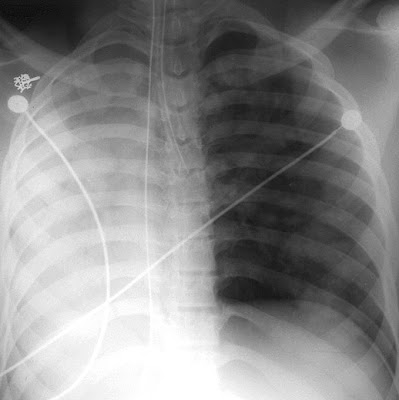

Normal ocular ultrasound